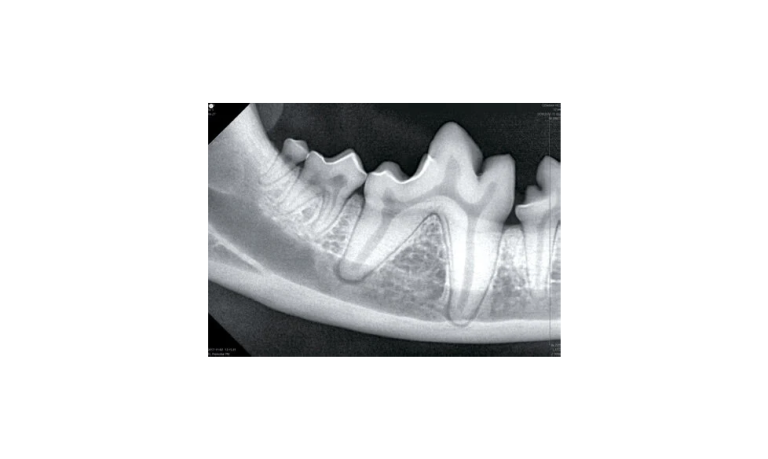

Ray W dental x-ray

Wall-Mounted Dental X-Ray

- Weight innovation with CNT (Carbon Nanotube) technology

- Lower dose to user

- Greater longevity

- Consistent target exposure

- Stable high efficiency energy

- Smart angulation for optimal result

MyVet Ray W can optimize an image exposure setting based on the angle of the tube head. - Secure clear images with a 0.4 mm focal spot

Regardless of which intraoral sensor you use, the MyVet Ray W minimizes blur and provides additional diagnostic value with a 0.4mm focal spot

Ez sensor intraoral

- Superior image quality with CMOS technology

- Three sizes to accommodate all intraoral applications 1.0, 1.5 and 2.0

- Slim lightweight design for patient comfort

- Water and dust resistant

- Robust & durable ultra flexible fiber optic cable

- User-friendly easy to use dental imaging software